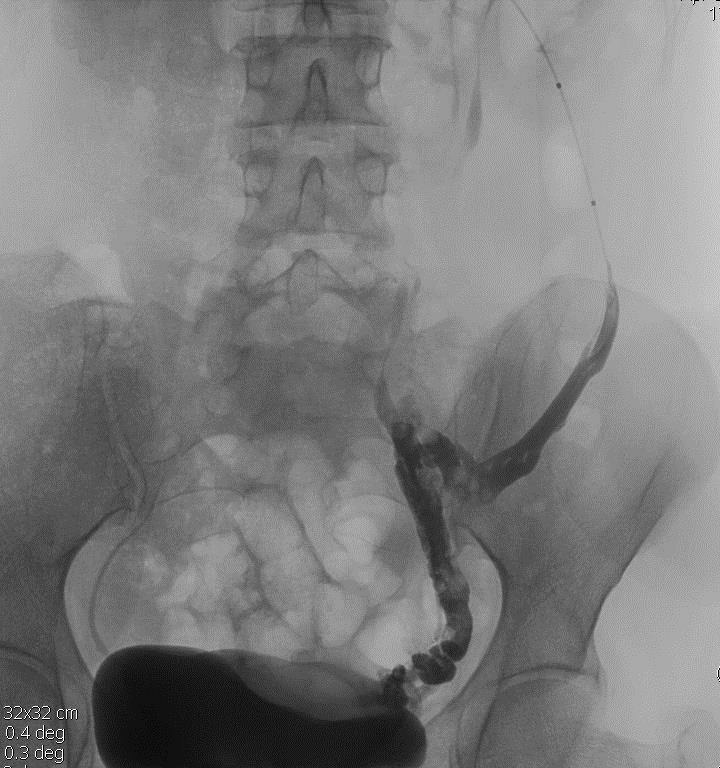

Recognize the ultrasound, CT angiography, and catheter angiography findings of Nutcracker Syndrome

Nutcracker SYNDROME: The constellation of clinical symptoms and radiologic findings resulting from pathologic LRV compression/stenosis and resulting collateralization 胡桃夹子综合征:由病理性左肾静脉压迫/狭窄和侧支导致的一系列临床症状和影像学表现 左肾静脉高压(早期): 血尿和后背疼痛 LRV Hypertension (early stage) Essential hematuria and flank pain

1. development of venous collateral vessels which increases venous capacitance()

2. Competence of the venous valves of the OV or LV

3. Development of direct communication between the dilated venous sinuses and adjacent calyces

4. Flank pain/hemoturia/orthostatic proteinuria 左肾静脉高压(中期):典型的盆腔充血综合症的症状